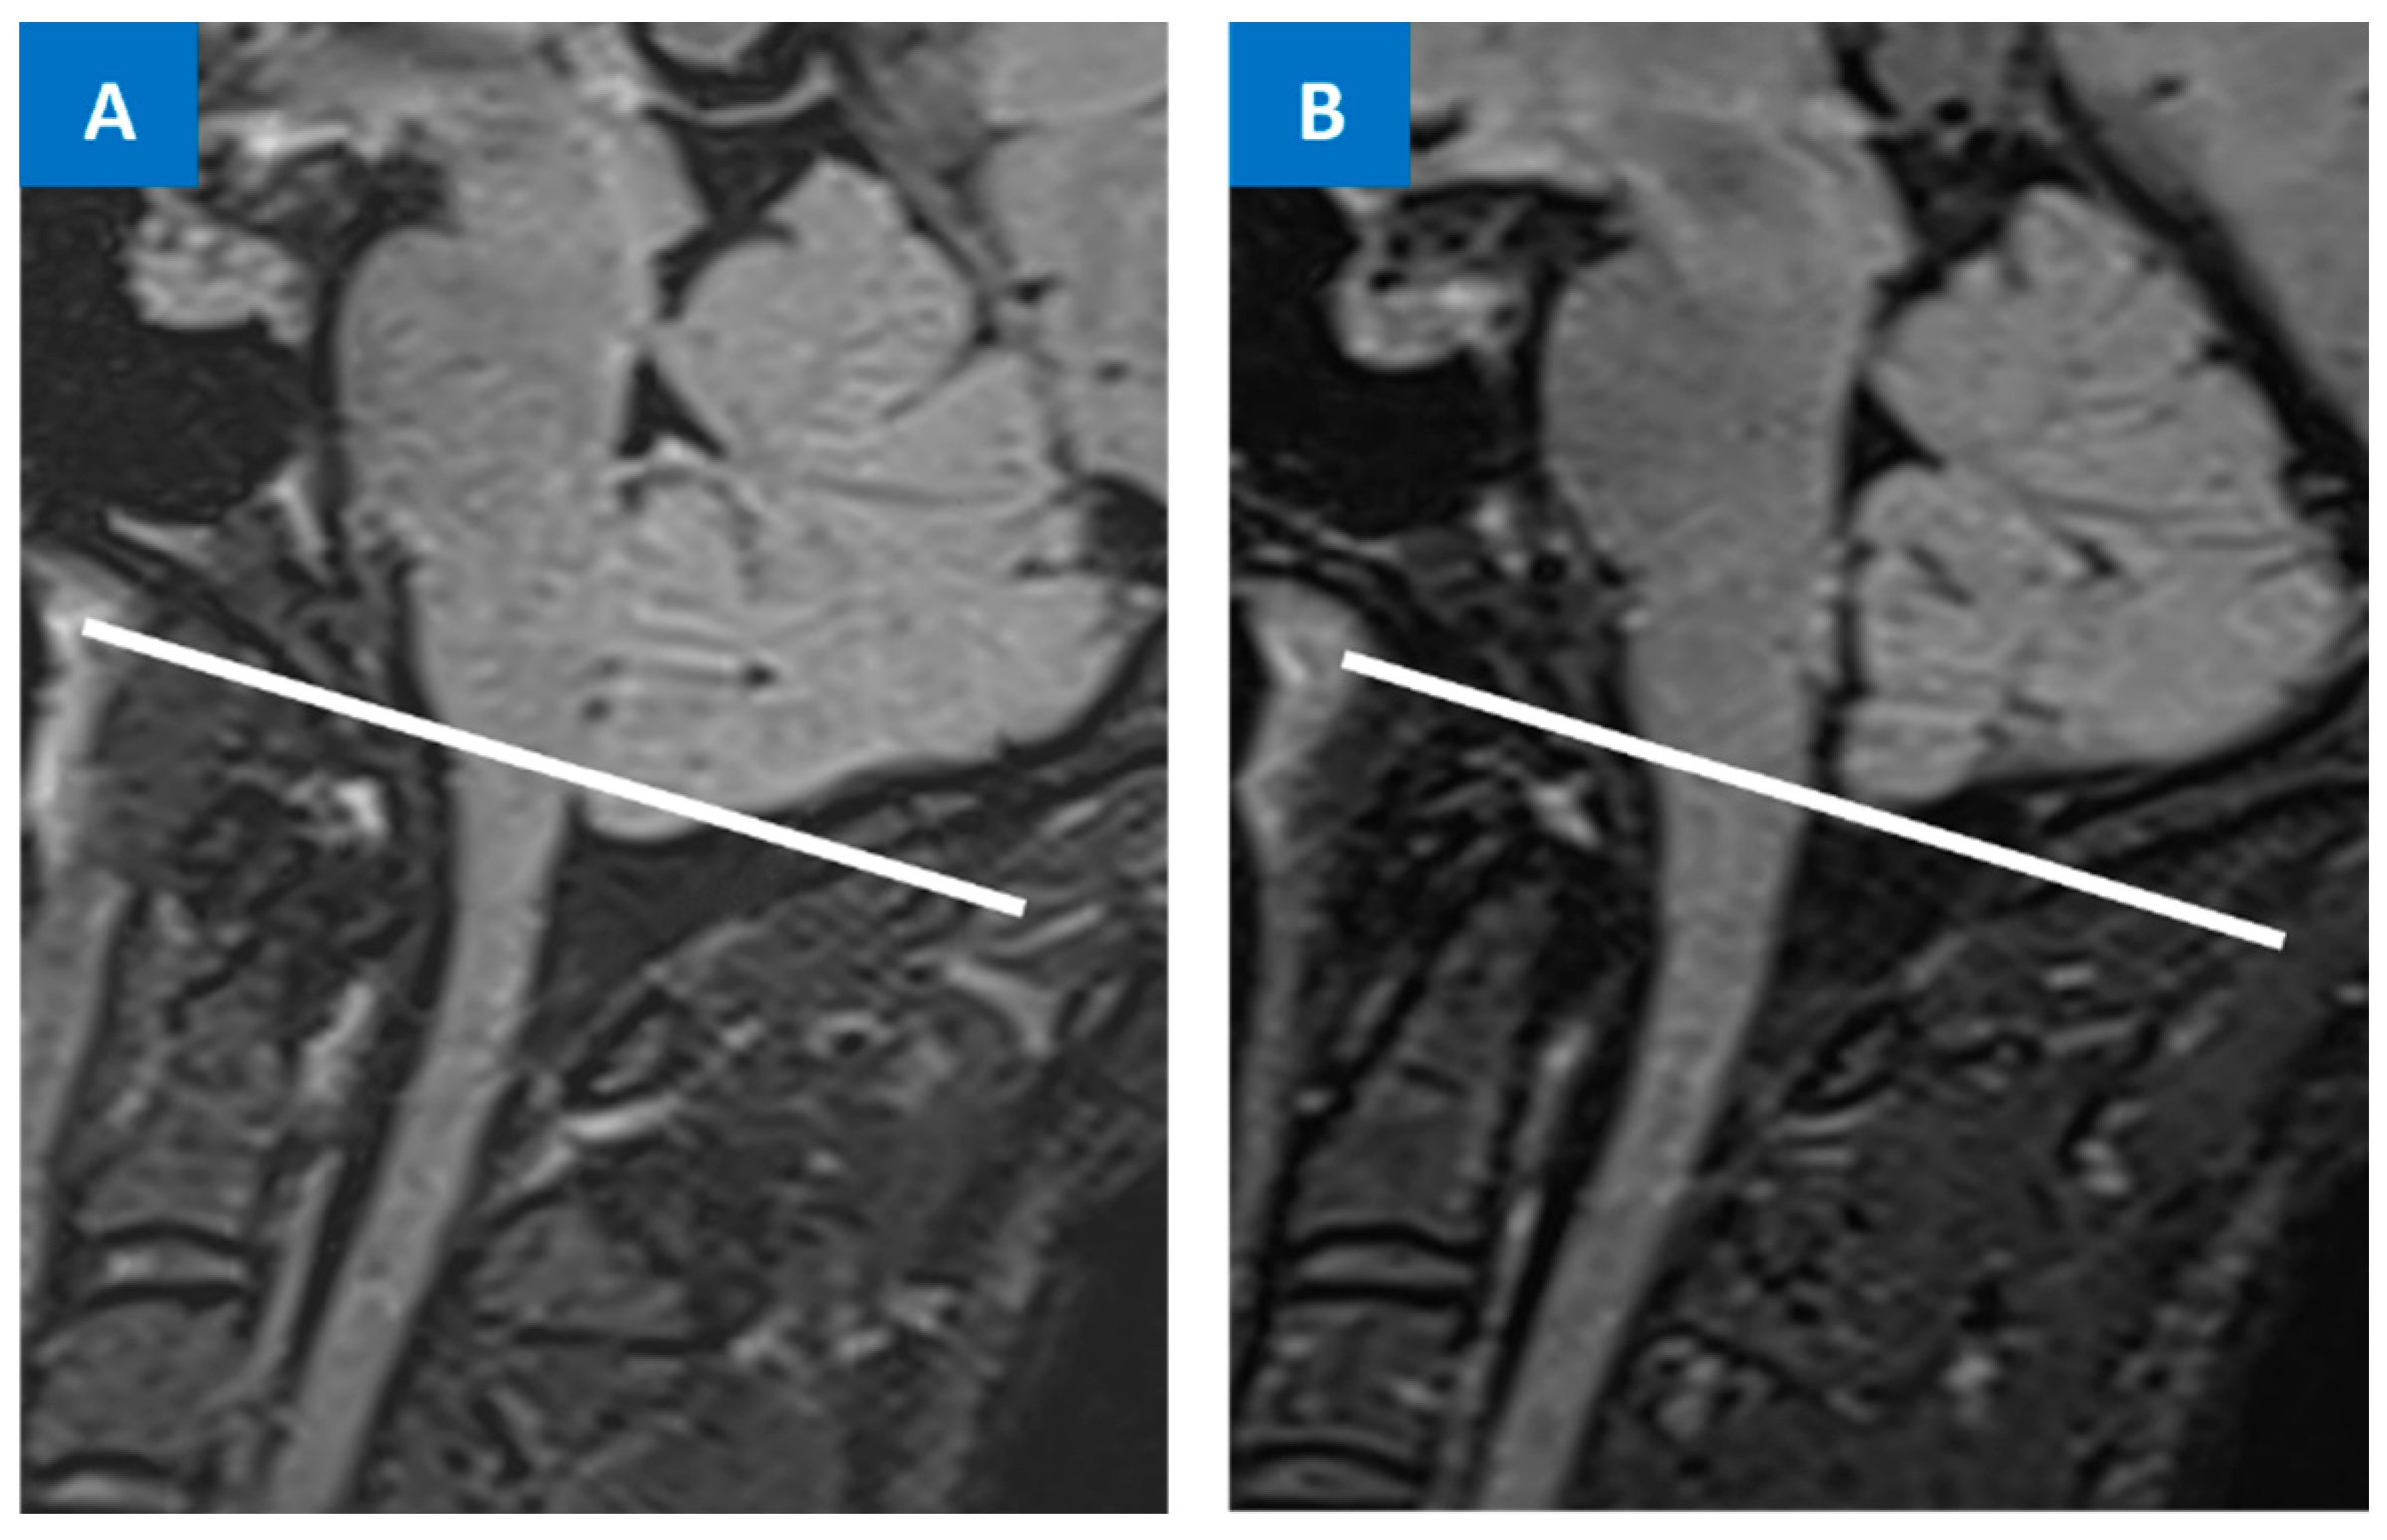

5.1. Head MRI

5.2. Spine MRI

6. Differential Diagnosis between SIH and Chiari Malformation Type I